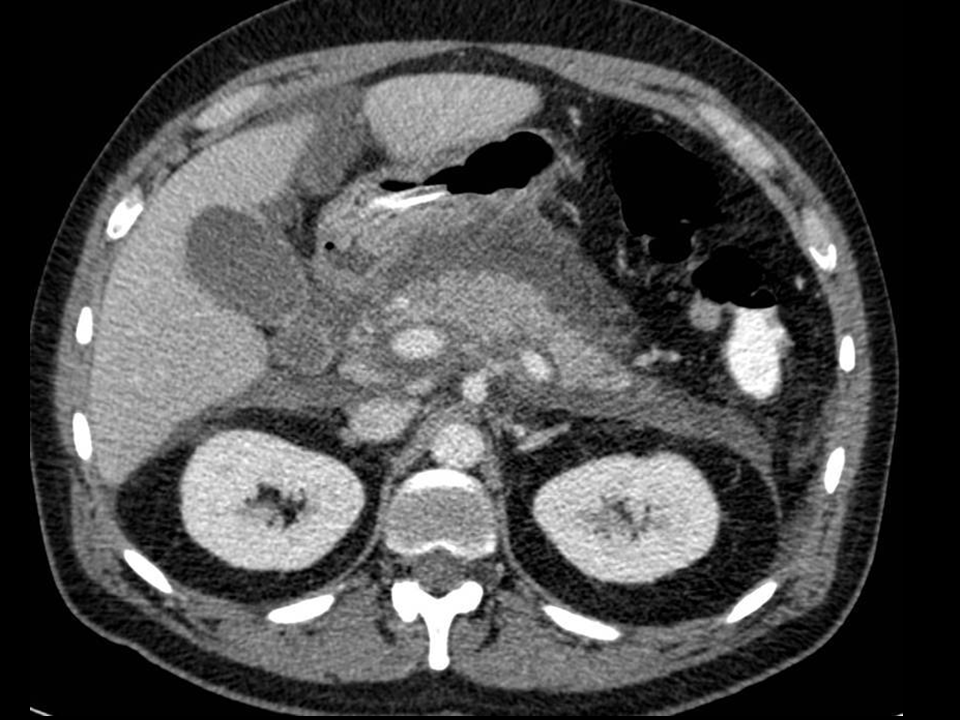

20. Acute pancreatitis. CT examination reveals peripancreatic fluid collection in the anterior pararenal space. The pancreas is edematous.